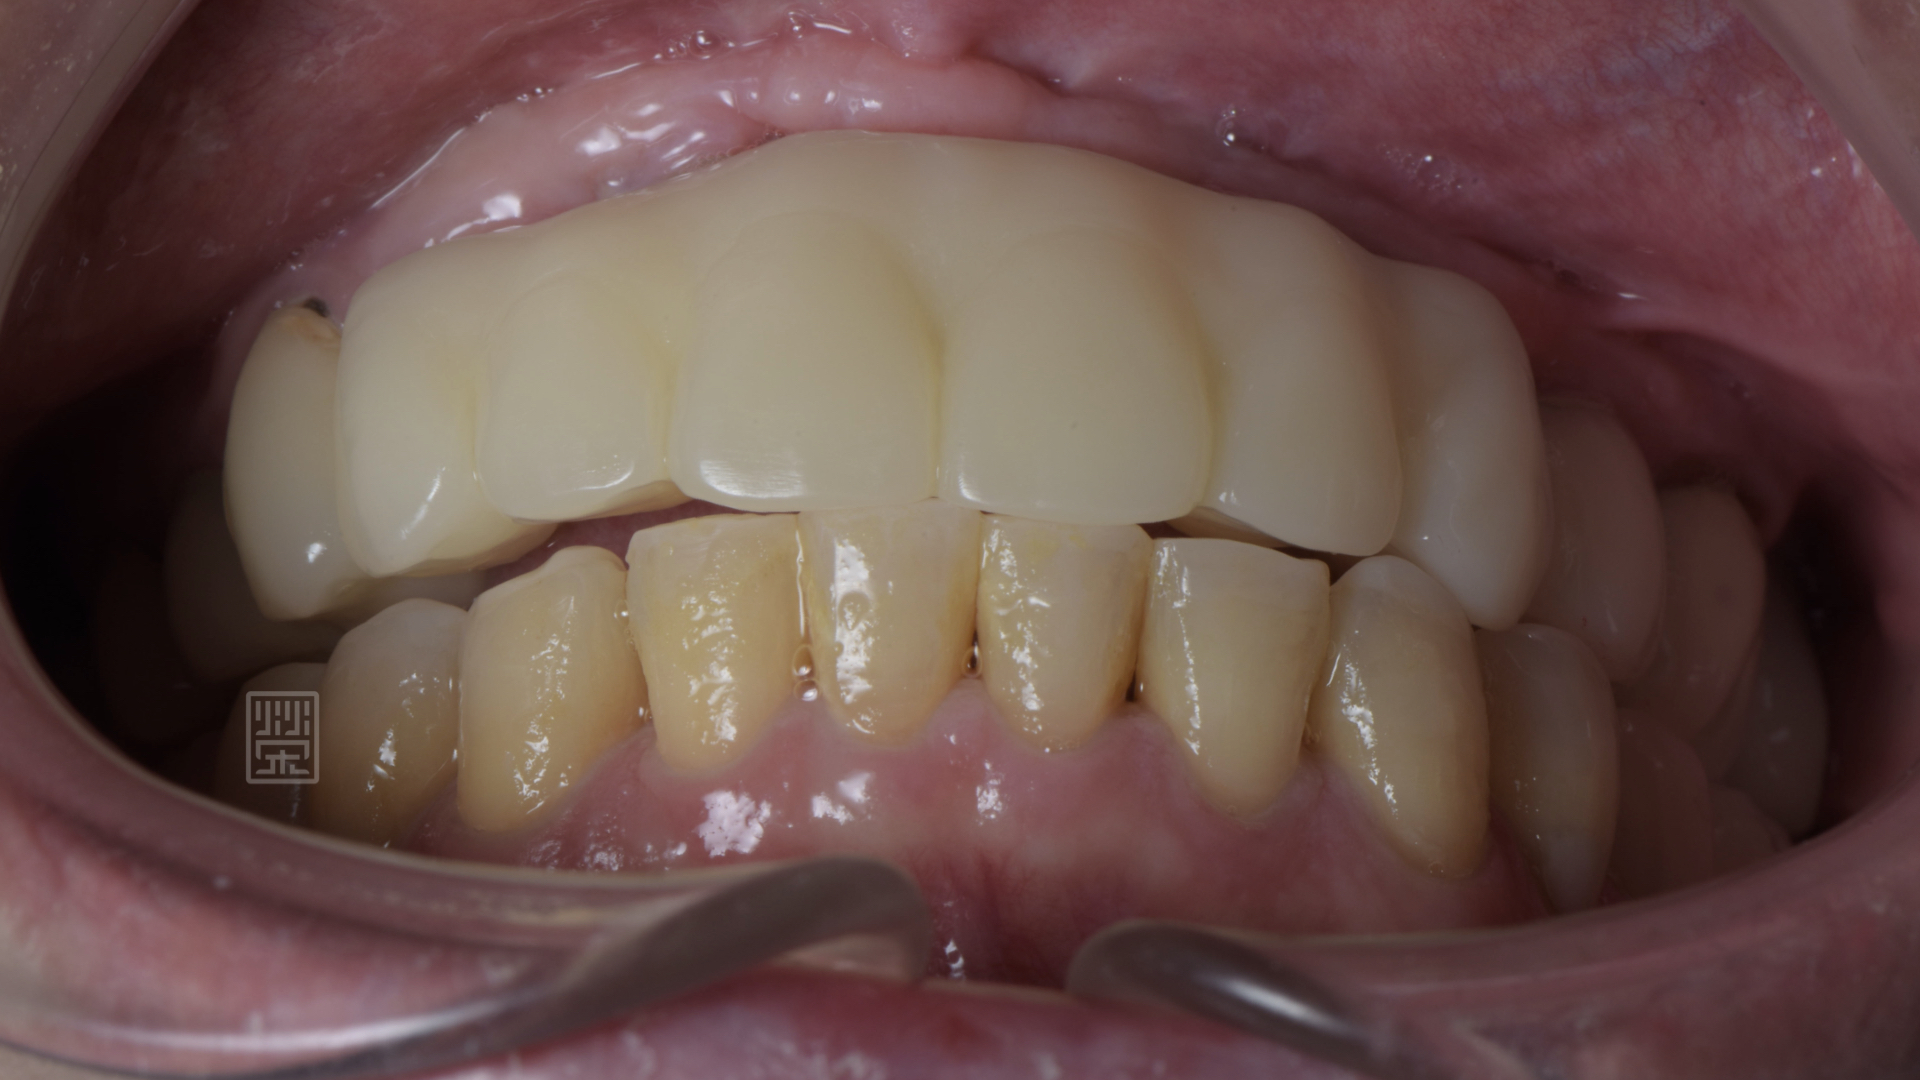

更換臨時假牙後,恢復外觀與功能